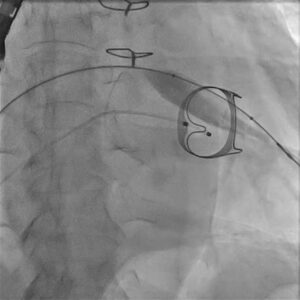

Figure 2. Fluoroscopic still during transcatheter valve positioning across the degenerated surgical mitral bioprosthesis.

A successful TMVR procedure begins well before the catheter enters the body. Careful case planning is essential to understand the dimensions of the prior surgical valve, the feasibility of transcatheter placement, access route considerations, and the risk of procedural complications. In complex valve-in-valve procedures, fluoroscopy and echocardiographic guidance are central to accurate positioning and deployment.

In this patient, the old surgical prosthesis had to be crossed and assessed with precision. The transcatheter valve system was then advanced and aligned within the failed bioprosthetic mitral valve. Exact orientation and deployment depth are crucial, because even a small positional error can affect prosthesis seating, gradients, and overall function.

The procedural stills from the uploaded case video help visualise this journey from catheter setup to valve positioning, expansion, and final stabilisation.